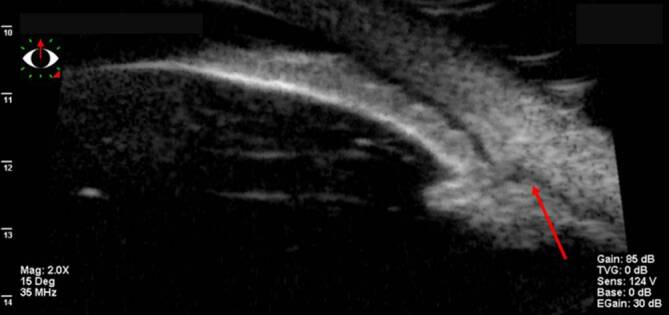

zum Nachweis von Ziliarkörper- oder Aderhautveränderungen (Abb. 9) ist nur eingeschränkt nützlich [37]. Eine Zyklodialyse sowie pathologische Veränderungen im Bereich des Ziliarkörpers und Kammerwinkels lassen sich besser mit der UBM nachweisen (Abb. 10; [38, 8, 35, 37]). Bei mit Silikonöl gefülltem Bulbus und einem Zyklodialysespalt in der oberen Hemisphäre kann das Silikonöl in sitzender Position den Spalt verschließen und so die OCT-Untersuchung des vorderen Augenabschnitts verfälschen – hier empfiehlt sich die Untersuchung auch mit zur Seite geneigtem Kopf des Patienten.

Für die Ultraschallbiomikroskopie

Ultraschallbiomikroskopie

bestehen prinzipiell 2 Möglichkeiten: Über einen auf den Bulbus gesetzten und mit Wasser gefüllten Trichter wird der UBM-Schallkopf an die Oberfläche angekoppelt. Die Alternative besteht in einem Kunststoffüberzieher (z. B. der Finger eines Operationsgummihandschuhs), der mit z. B. BSS (physiologische Kochsalzlösung) gefüllt ist und der mittels Kontaktgel (z. B. Hydroxymethylcellulose) an die Augenoberfläche angekoppelt wird. Dies ist auch transpalpebral möglich. Meist kommen 2 UBM-Schallköpfe für die Diagnostik zum Einsatz: ein 35-MHz- und ein 50-MHz-Schallkopf. Der 50-MHz-Schallkopf bietet eine höhere Auflösung, eine geringere Eindringtiefe und einen kleineren Bildausschnitt des Auges. Wir verwenden meist den 35-MHz-Schallkopf, weil damit ein größerer Augenausschnitt im Vorderabschnitt dargestellt werden kann.